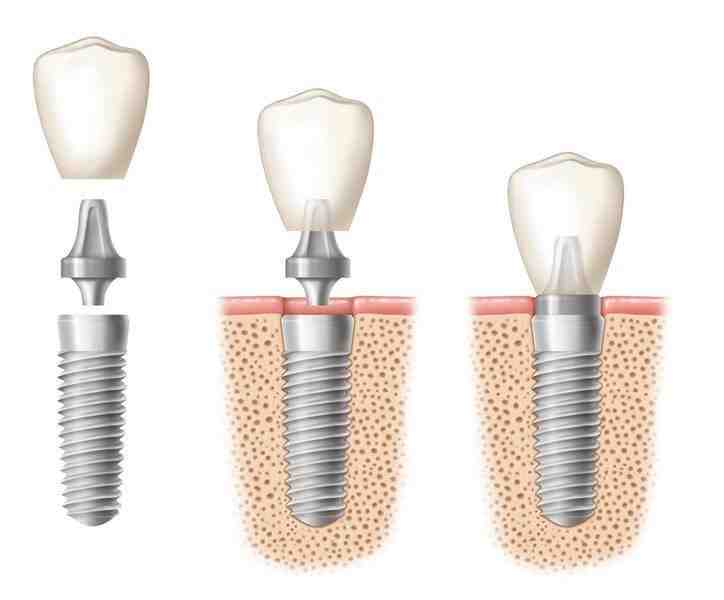

When maintained with proper hygiene and examinations, dental implants can last a lifetime. The crown attached to the implant will usually need to be replaced every 15 to 20 years, although in some cases it can take several decades.

How long do titanium dental implants last?

With a titanium root and a porcelain crown, a dental implant could last up to 25 years.